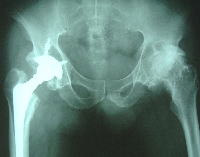

人工関節置換術

図5:人工関節

人工関節 は進行期や末期の患者さんに行います。これも良い手術方法で、痛みもなくなりますし、動きも良くなります。ですからとてもよい手術なのですが、問題は人工の関節は一生もつわけではないということなのです。どの位もつかと言うのは人によって様々です。その患者さんの体重や活動具合、骨の強さなどによって10年で再手術が必要になったり、20年も30年ももつ方もいます。そこで通常は50歳以下の患者さんには行いません(図5)。